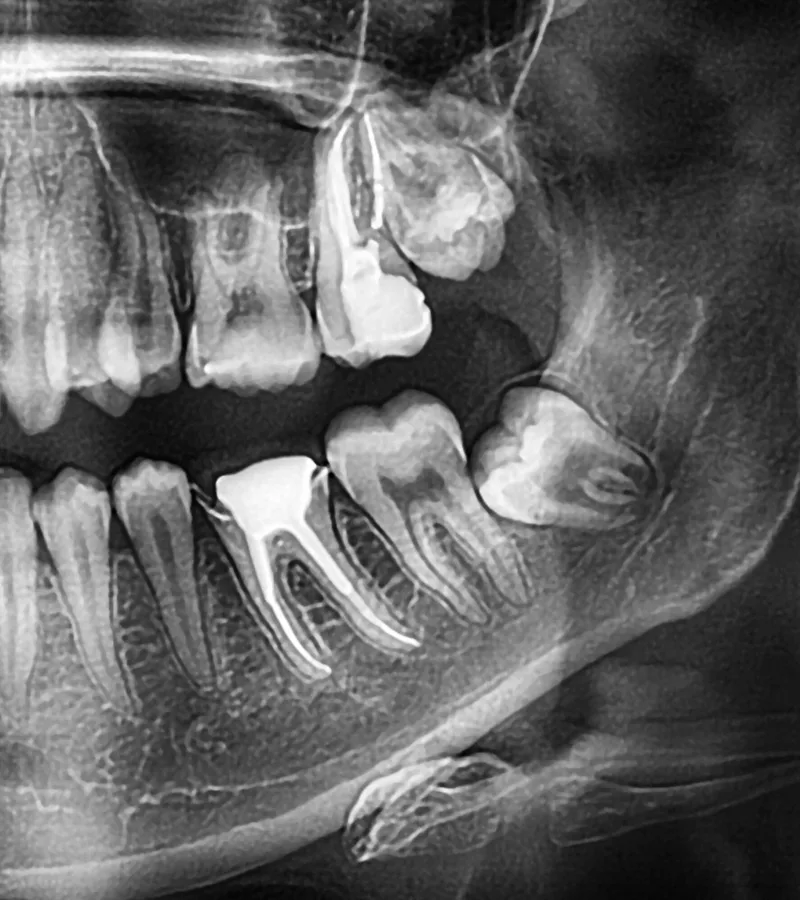

Is an X-ray necessary for wisdom teeth removal?

Most individuals require an OPG (Panoramic) X-ray, which we can perform at our clinic. This x-ray shows the impacted wisdom teeth and other critical structures. If the teeth’s roots overlap with nerves, a more specialized cone beam CT scan, available at our clinic, may be needed.